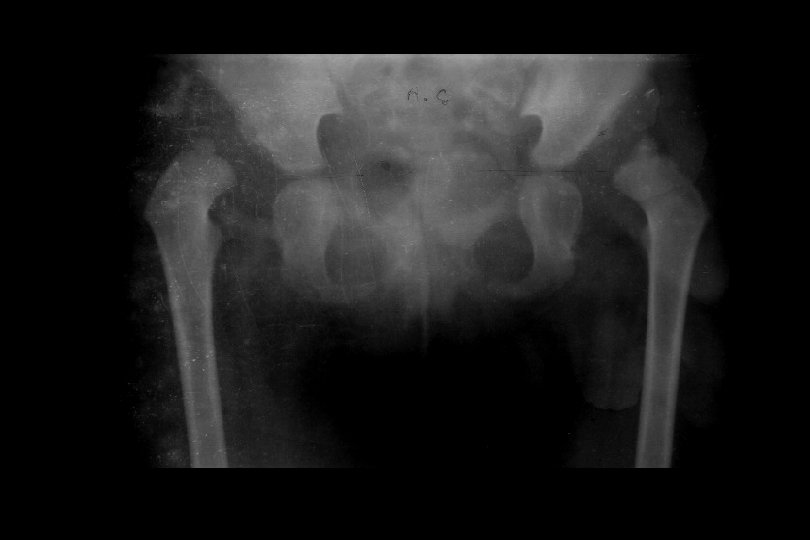

Genç adult Reluksasyon Hareket kısıtlılığı Avasküler nekroz Displazi, sublukse kalçalarda Ase-femur baş uyumunu artıran Girişimler Tamamen çıkıklara dokunulmamalı !!!

Sekonder dejeneratif osteoartrit TEMAS ALANI = 26. 7 cm Birim alana düşen yük miktarı = 23 kg/cm 2 TERS ORANTI

Adult • Artrodez !!! • Total Eklem Replasmanı • Genç ve aktif yaştalar • İyileştirilmiş malzemeler kullanılmalı • Hasta çok detaylı bilgilendirilmeli